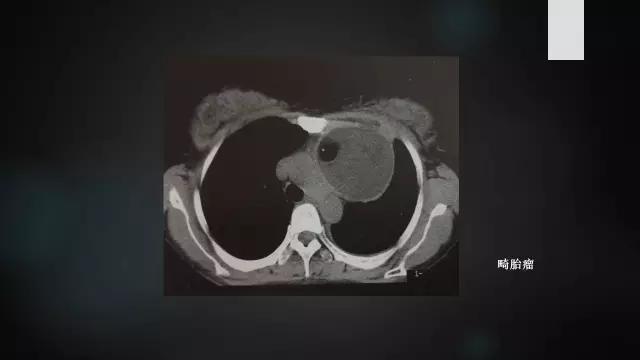

畸胎瘤

畸胎瘤(teratoma)是由2~3个胚层的多种组织构成的肿瘤。畸胎瘤分为囊性和实质性两类。囊性畸胎瘤又称为皮样囊肿, 含外胚层及中胚层结构, 囊内为皮脂样液体。实性畸胎瘤组织成份复杂, 含外、中、内三胚层结构。畸胎瘤病理分为:①成熟型畸胎瘤,即良性畸胎瘤,由已分化成熟的组织构成。②未成熟型畸胎瘤,即恶性畸胎瘤,由胚胎发生期的未成熟组织结构构成,多为神经胶质或神经管样结构,常有未分化、有丝分裂增多的恶性病理表现。

本病20~40岁多见,80%为良性,常位于前纵隔中部,肿瘤较大时出现胸痛、咳嗽、胸腔积液、咳出毛发等症状。

2.CT表现:前纵隔内边缘光滑的厚壁囊性肿块,囊壁常有钙化,病灶内密度不均匀,囊内出现脂肪、脂液平面、骨骼、牙齿等为特征性表现。少数病灶以软组织成分为主,形成实性畸胎瘤。如出现周围脂肪层不清、邻近结构受累,则提示恶性畸胎瘤可能。